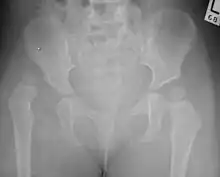

Hip dysplasia diagnosed by ultrasound[40] and projectional radiography ("X-ray").[41] Ultrasound imaging is generally preferred at up to 4 months due to limited ossification of the skeleton.[39][notes 1]

Despite the widespread of ultrasound, pelvis X-ray is still frequently used to diagnose or monitor hip dysplasia or for assessing other congenital conditions or bone tumors.[42] The most useful lines and angles that can be drawn in the pediatric pelvis assessing hip dysplasia are as follows:[42] Different measurements are used in adults.[42]